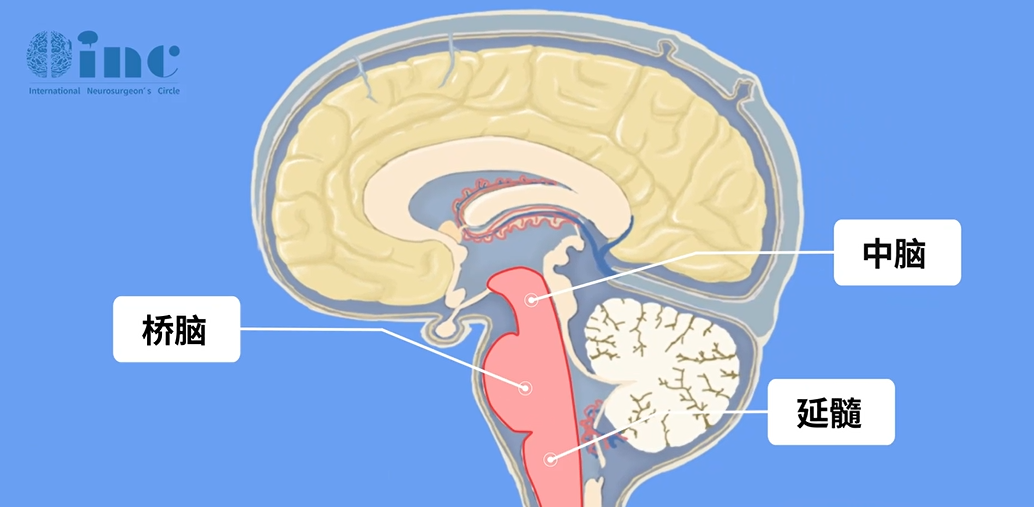

▼脑干所处位置示意:正常形态下

脑干是大脑的后部,与脊髓连续。脑干如人拇指大小,分为桥脑、延髓、中脑。处于大脑的“中心区”,是呼吸、心跳中枢,掌管负责人体肢体、脸部和眼球运动、意识等关键功能。临床常见的症状包括头痛头晕、肢体麻木无力、面瘫、复视、吞咽困难、饮水呛咳等。